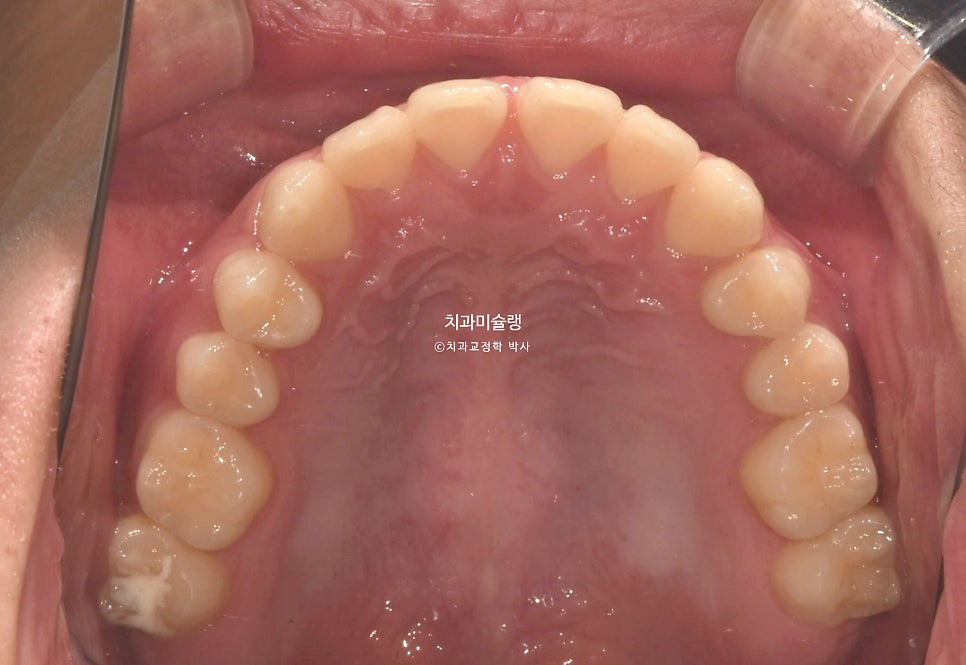

위 앞니가 벌어져있고 일부 개방교합이 보입니다.

어금니 교합관계는 3급이며 윗니가 아랫니를 덮지 못하는 절단교합 입니다.

아래턱이 위턱에비해 앞으로 더 자라나온 골격성 3급 부정교합, 즉 주걱턱 입니다.

양악 수술 없이도 교합은 맞춰줄수 있는 정도라 교정만 하기로 했습니다.